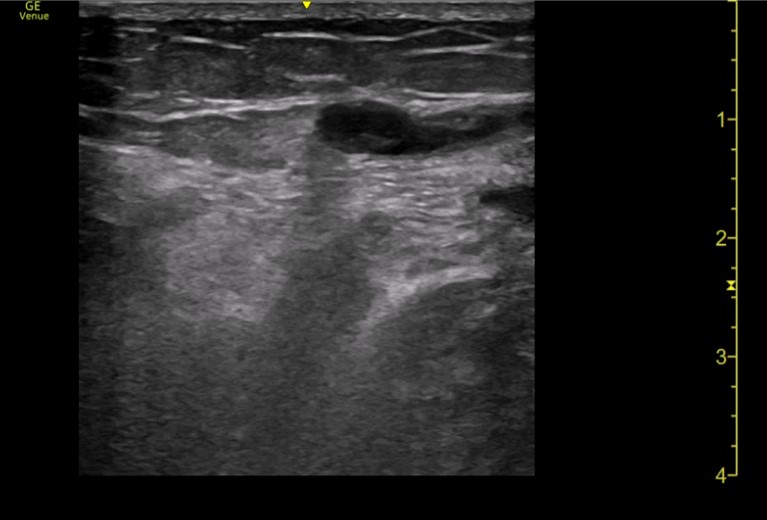

Ecografía a pie de cama: Con sonda lineal, se comienza visualizando vena femoral profunda, la unión de vena safena mayor y la vena poplítea, todas ambas con buena compresión. Por último, se visualiza región dolorosa del paciente, donde se observa vena superficial con contenido hiperecogénico en su interior y ausencia de cambios con la compresión. Se delimita dicha región con longitud inferior a 5 cm y a más de 5 cm de unión safeno-poplítea.